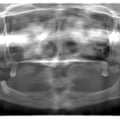

Максимальна атрофія щелеп - результат тривалого користування знімними протезами